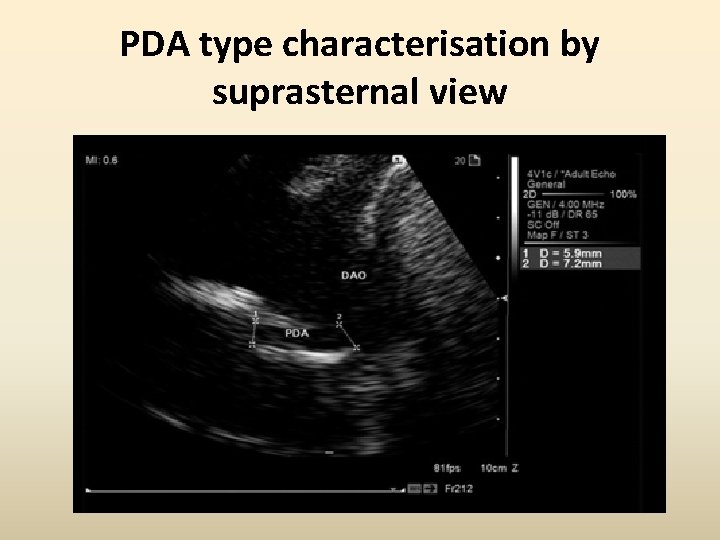

PDA type characterisation by suprasternal view

Measurements from the suprasternal view -Ampulla -Adjacent aortic diameter.

Use of 2 D Echo in pre-interventional work up • Minimum diameter (A) • Length (B) • Ampulla diameter (C) • PDA type

Use of 2 D Echo in pre-interventional work up • Echo classification corresponding to Krichenko’s A- Conical with a narrow pulmonary end B- Short with narrow aortic end C- Tubular without constriction D- Multiple constrictions E- Long and tortuous requiring >1 echo plane for complete imaging Comprehensive Assessment of Patent Ductus Arteriosus by Echocardiography Before Transcatheter Closure. J Am Soc Echocardiogr 2002; 15: 1154 -9.